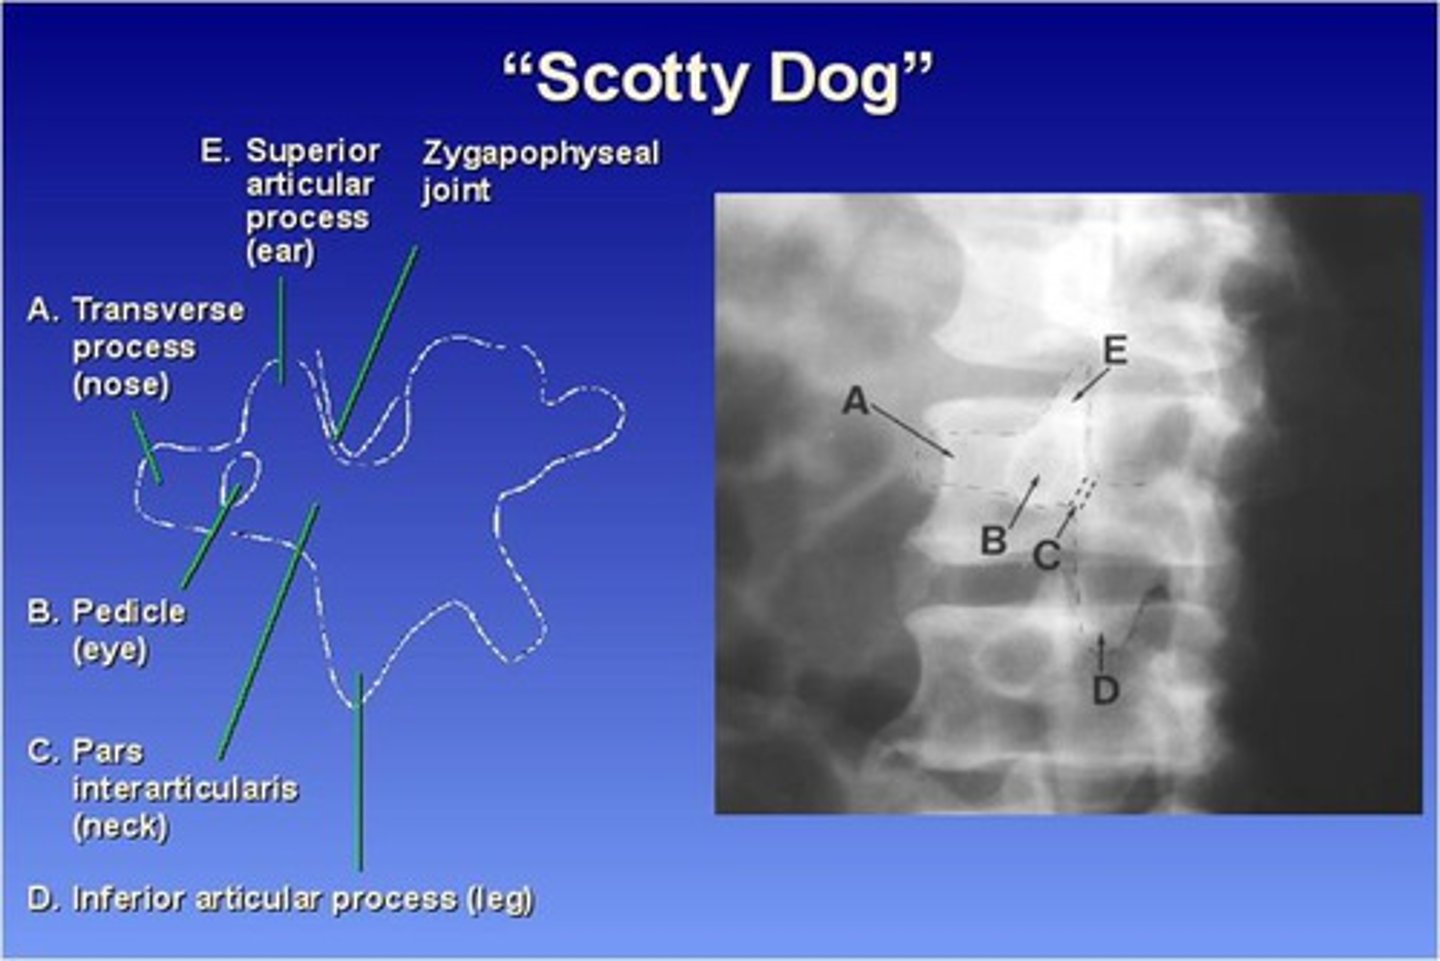

The Lumbar zygapophyseal joints are ONLY demonstrated on what view?

45 degree obliques (will see "scotty dog")

What part of the lumbar spine makes up the "nose" of the "scotty dog"?

transverse process

What part of the lumbar spine makes up the "eye" of the "scotty dog"?

pedicle

What part of the lumbar spine makes up the "neck" of the "scotty dog"?

pars interarticularis

What is the pars interarticularis?

portion of each lamina between the superior and inferior articular processes

What part of the lumbar spine makes up the "leg" of the "scotty dog"?

inferior articular process

What part of the lumbar spine makes up the "ear" of the "scotty dog"?

superior articular process